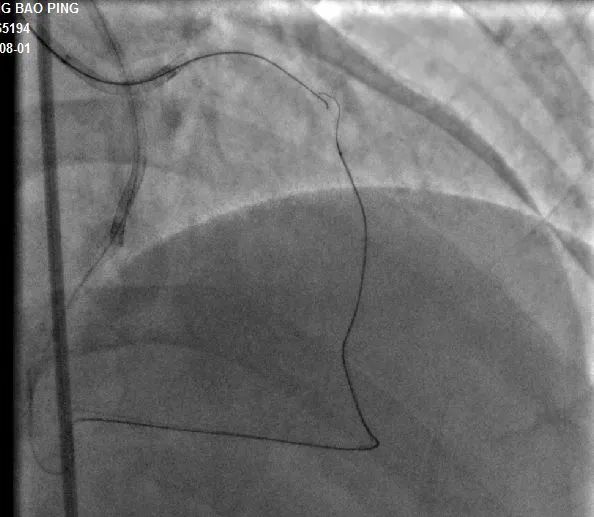

▲术中逆向通道建立

手术过程:7F LA1.0指引导管到位RCA开口,SionBlue(0.014”、0.5g)导丝送至后降支(PD3 )作为逆向导丝进入间隔支,以tip-injection技术进行间隔支超选择性造影,以明确逆向通路走形。逆行进入LAD中段,再次以tip-injection技术进行超选择性造影以明确LDA闭塞段以远情况,操纵导丝逆向行进至LAD中段闭塞段以远,尝试穿过闭塞段逆行到达LAD近段,推送逆向微导管通过闭塞段进入正向指引导管内,缓慢退出逆向系统至右冠内,逆向造影显示通路安全,撤出逆向系统。顺利预处理闭塞段病变后,于LAD近中段植入两枚支架,优化支架后,结果满意。